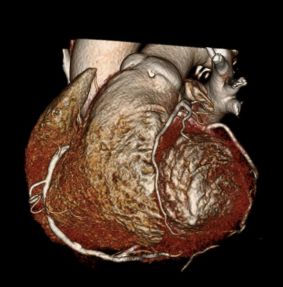

Heart CT is a fast screening exam done without contrast on a 16-slice CT scanner at RAYUS centers throughout Puget Sound. The scan allows us to non-invasively look at the three major coronary arteries that carry blood to your heart muscle.

With Heart CT, we can detect and measure the size and density of calcified plaque, presenting that as a quantitative score. The higher the calcium score the greater the amount of underlying CAD and the greater the risk of a subsequent cardiac event.